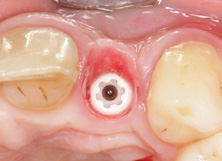

Der klinische Befund zeigte eine definitive Versorgung auf 12 und eine temporäre Versorgung auf 22. Dahingegen lag bei der Implantatversorgung in regio 22 der Verdacht auf eine partielle Fibro-Osseointegration vor (Abb. 1 und 2) [9,10].

Nach sechs Monaten Einheilzeit war der labiale Aufbau in einen stabilen Knochen umgebaut und das CERALOG Implantat osseointegriert. Nachdem die Klebebrücke herausgetrennt war, wurde das Implantat mittels modifizierter Rolllappentechnik freigelegt. Der Anteil der krestalen Gingiva über dem Implantat wurde mit einem diamantierten Schleifkörper deepithelisiert (Abb. 15). Mit einem wellenförmigen parakrestalen Schnitt wurde der Zugang zur Implantatverschlusskappe geschaffen, indem das nach labial gestielte Weichgewebe über dem Implantat mobilisiert und angehoben wurde. Anschließend wurde die flache Kappe entfernt und ein 4 mm hoher Gingivaformer eingeschraubt. In das labiale Weichgewebe wurde eine Tasche über dem Periost präpariert, in die das umgeklappte Bindegewebe eingeschoben wurde (Abb. 16–19). Mit einem 6.0 Prolene-Nahtmaterial wurde das Weichgewebe dicht um den Gingivaformer vernäht (Abb. 20). Die von basal gekürzte temporäre Klebebrücke befestigten wir adhäsiv an den Nachbarzähnen.

Nach einer Ästhetikeinprobe wurde die Zirkoniumdioxidkrone mit Multilink Hybrid Abutment Zement (Ivoclar Vivadent) auf dem PEKK-Abutment verklebt (Abb. 25–28). Die Klebeüberschüsse wurden entfernt, die subgingivalen Anteile sorgfältig poliert und gereinigt. Die Abbildung 29 zeigt das individuell ausgeformte Weichgewebsprofil vor der definitiven Insertion der Hybridabutmentkrone, die mithilfe einer neuen Titanabutmentschraube eingesetzt wurde. Nach dem Einsetzen der Versorgung mit 25 Ncm wurde eine Röntgenkontrollaufnahme angefertigt. Da das Hochleistungspolymer nicht röntgenopak ist, bedarf es etwas Erfahrung bei der Passungskontrolle. Die Aufnahme sollte im rechten Winkel zur Plattform auftreffen, um dann eine parallel verlaufende dunkle Scheibe in einer Höhe von 0,55 mm über dem Implantat zu erkennen (Abb. 30 und 31). Mithilfe von Zusätzen, wie z. B. Bariumsulfat, könnte der Hochleistungskunststoff röntgenopak gefertigt werden. Allerdings würden diese das Material schwächen, wodurch die herausragenden Eigenschaften von PEKK, wie Stabilität, Duktilität und Abdichtung, minimiert würden. Beim Followup nach zwölf Monaten zeigten sich eine stabile Weichgewebesituation und geschlossene Interdentalräume (Abb. 32).